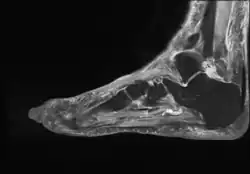

Diagnosis

The diagnosis of bursitis can be done via a musculoskeletal ultrasound[5]